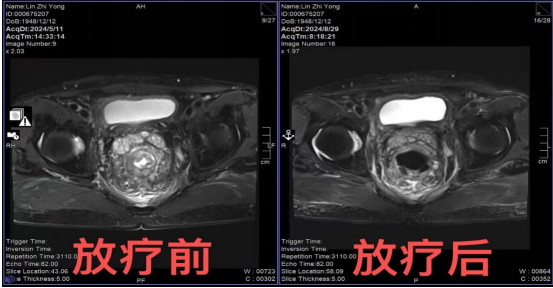

近日,一例76岁老年男性患者,经肠镜及病理活检确诊为直肠腺癌,转入肿瘤中心消化泌尿病区,在肿瘤中心主任医师林思祥的主持下第一时间行多学科MDT讨论,结合目前国内外最新指南最终确定方案为:局晚期直肠癌,分期T3N2aM0,首选新辅助放化疗+TME手术,术后依据病理结果行辅助化疗。患者接受诊疗方案,在我院肿瘤中心消化泌尿病区接受新辅助放化疗(7野调强放疗50Gy/25F,同步卡培他滨口服化疗),放化疗过程顺利、胃肠道及骨髓毒性反应1级,8周后于胃肠外科手术,术后病理回报:肿瘤退缩分级(AJCC)TRG 0级,无癌细胞残留,达到病理完全缓解(pCR)。